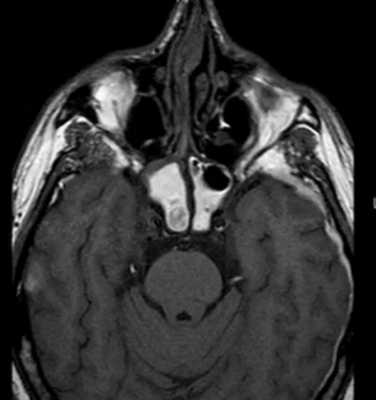

Метод применяют для диагностики новообразований, при подозрении на инфекционно-воспалительные процессы, гнойное расплавление тканей. По снимкам МРТ планируют лечебные хирургические вмешательства, пластические операции, вспомогательные процедуры при диагностике различных опухолей (менингиома, остеома, остеобластома и пр.). Основные данные о состоянии костей получают при КТ.

Взрывной перелом орбиты на МРТ (изменения указаны стрелкой)